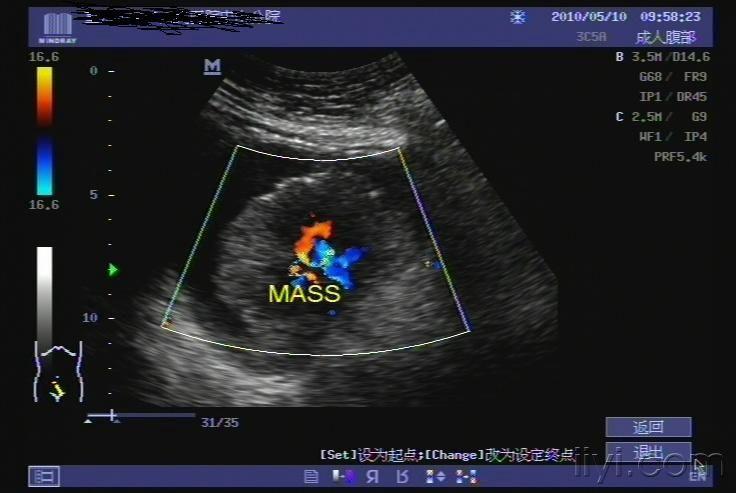

超声入门贴41膀胱癌

图片尺寸768x576